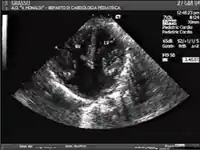

DSAVs podem ser detectados por ausculta cardíaca ; eles causam sopros atípicos e batimentos cardíacos altos. A confirmação dos achados da ausculta cardíaca pode ser obtida com um ultrassom cardíaco ( ecocardiografia - menos invasivo) e cateterismo cardíaco (mais invasivo).

O diagnóstico provisório também pode ser feito no útero por meio de ecocardiograma fetal. Um diagnóstico de AVSD feito antes do nascimento é um marcador para a síndrome de Down, embora outros sinais e testes adicionais sejam necessários antes que qualquer confirmação definitiva de qualquer um possa ser feita.